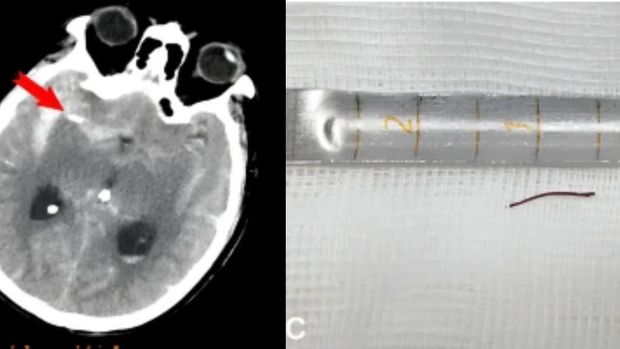

Berdasarkan hasil pemindaian, terlihat ada jarum akupunktur berwarna emas dan agak runcing sepanjang setengah inci atau sekitar 1,27 cm itu bersarang di dalam arteri otak pria tersebut. Hal itu menyebabkan perdarahan internal yang berdampak pada masalah ingatannya.

Jarum akupunktur tertancap di otak pria selama 20 tahun Foto: Journal of Medical Case Reports |

Lebih lanjut, dokter terlebih dahulu harus memotong sebagian tengkoraknya atau prosedur yang disebut kraniotomi untuk melihat otaknya. Dokter kemudian memotong dura mater atau lapisan luar otak yang tebal, dan menggunakan mikroskop bedah untuk menavigasi otak dan jarum akupunktur yang tertancap tersebut. Ini bertujuan untuk menghindari arteri dan struktur vital.

Jarum kemudian dicabut, dan pembuluh darah yang pecah ditutup menggunakan klip logam yang sangat kecil untuk menutup bagian pembuluh yang pecah.